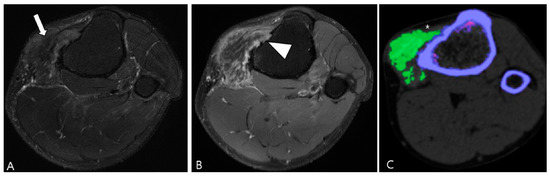

3.2. Differential Diagnoses of Extra-Articular D-TSGCT

3.2.1. Fibroma of the Tendon Sheath (FTS)

3.2.2. Extra-Abdominal Desmoid-Type Fibromatosis (DF)

2.5. Advanced MRI Sequences for D-TSGCT